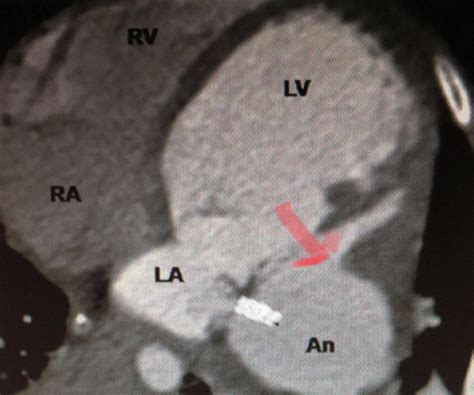

• Cardiac Magnetic Resonance Imaging (MRI): This provides detailed images of the heart and can help in diagnosing and assessing the severity of the aneurysm.

• Rupture: In severe cases, the aneurysm can rupture, leading to sudden death.

• left ventricular aneurysm ct

• left ventricular aneurysm vs pseudoaneurysm